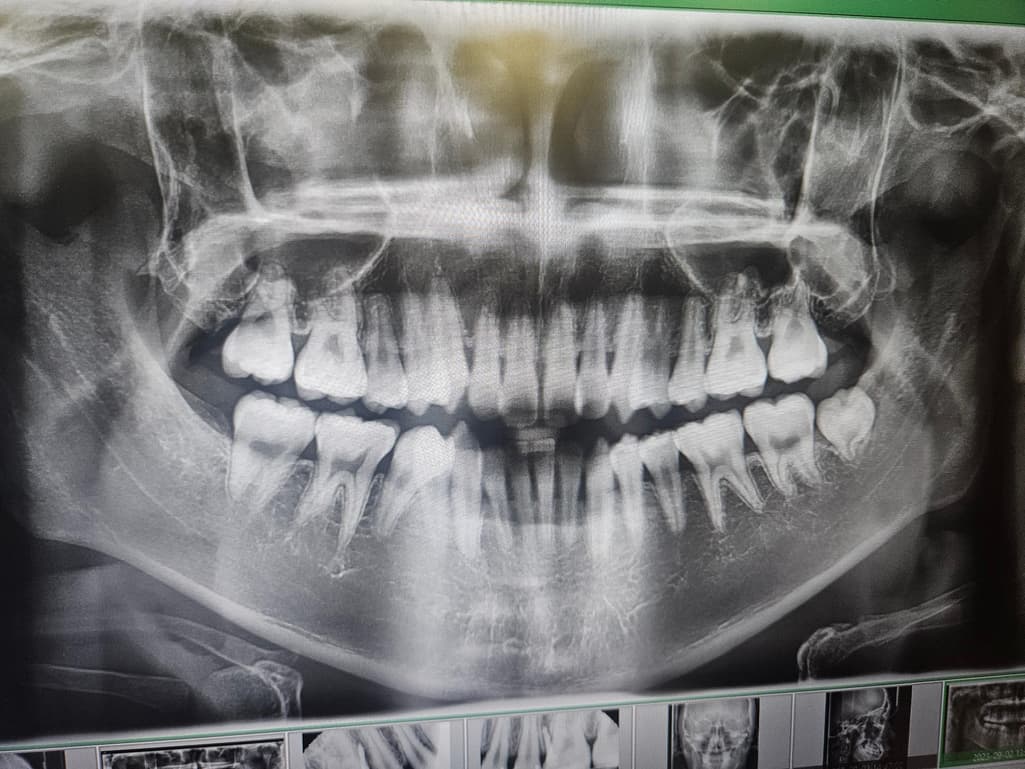

첫번째가 교정 시작할 때, 두번째가 현재입니다.

약 2년정도 되었고 육안으로 보기에도 잇몸이 많이 내려간 것 같은데 의견이 궁금합니다.

잇몸뼈가 꽤 내려간 것으로 보입니다. 교정 후에도 잇몸관리를 잘해주셔야 할 것 같습니다.

사진으로 갔을 경우에는 치조골의 양이 어느 정도 내려간 것으로 보입니다. 치즈볼의 양이 내려갔을 경우 치아를 잡고 있는 치조골의 양이 줄어들었기 때문에 잇몸에 염증이 생기지 않도록 주의해서 관리를 하는 것이 좋습니다.

엑스레이 사진으로는 잇몸이 아니고 잇몸뼈 상태를 관찰합니다. 교정 후로 잇몸뼈가 다소 낮아지고, 치아 뿌리도 짧아진 것이 관찰은 되지만 엄청 심각한 편은 아닙니다. 앞으로 관리 잘해주시면 됩니다. 교정 후 잇몸, 잇몸뼈 수축 그리고 치근 흡수 부작용은 얼마든지 있을 수 있습니다.